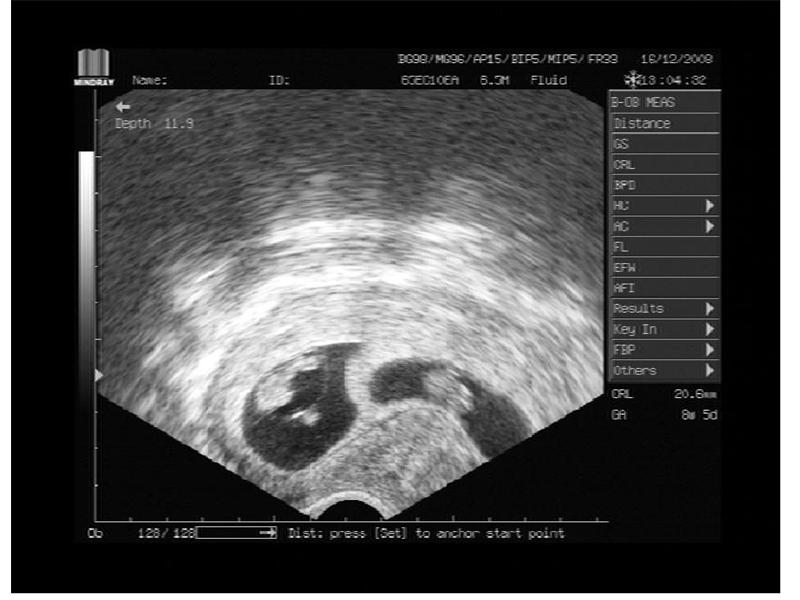

DVOJČÁTKA

už jsou o něco větší…